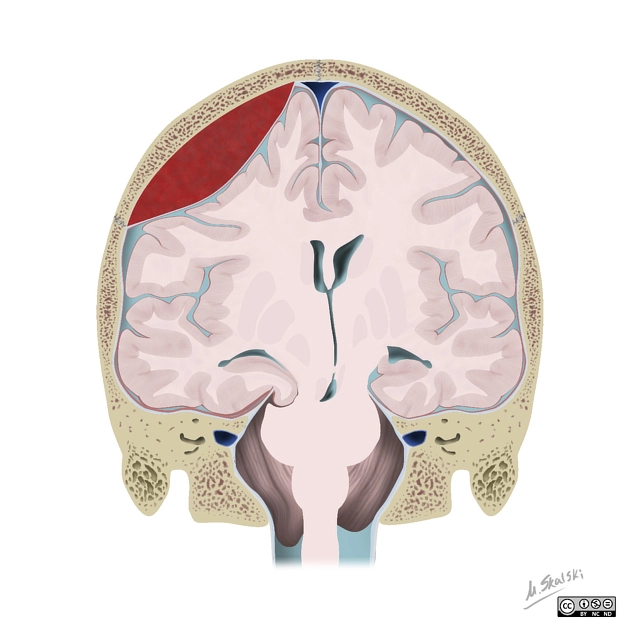

Xuất huyết ngoài màng cứng (Extradural Hemorrhage - EDH)/ Tụ máu ngoài màng cứng (Epidural Hematoma)

16/03/2026